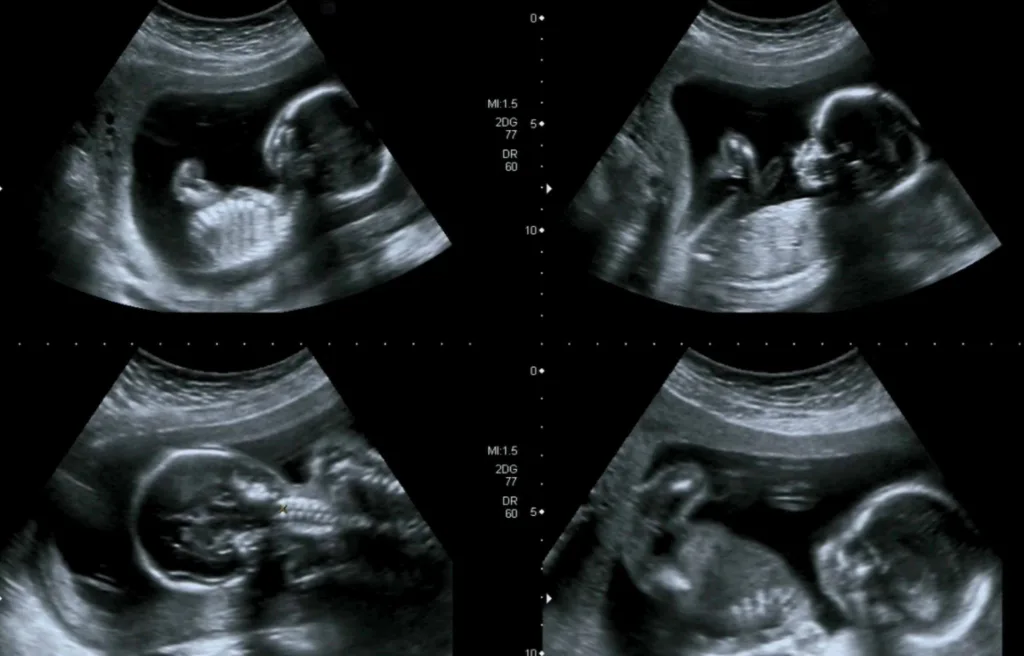

Die Frage, wann der letzte Ultraschall vor der Geburt stattfindet, ist eine, die viele Schwangere beschäftigt. In Deutschland sind die Vorsorgeuntersuchungen in der Schwangerschaft gesetzlich geregelt und beinhalten in der Regel drei Ultraschalluntersuchungen, eine pro Schwangerschaftsdrittel. Diese Untersuchungen sind für die Schwangere kostenlos.

Die Frage, wann der letzte Ultraschall vor der Geburt stattfindet, ist individuell und hängt von der jeweiligen Schwangerschaft und den Bedürfnissen der Schwangeren ab. In der Regel sind drei Ultraschalluntersuchungen während der Schwangerschaft vorgesehen, eine pro Schwangerschaftsdrittel. Im letzten Trimester der Schwangerschaft können zusätzliche Ultraschalluntersuchungen notwendig sein, wenn Komplikationen auftreten oder die Schwangerschaft als Risikoschwangerschaft eingestuft wird. Die Entscheidung, ob zusätzliche Ultraschalluntersuchungen notwendig sind, trifft der Arzt/die Ärztin in Absprache mit der Schwangeren.